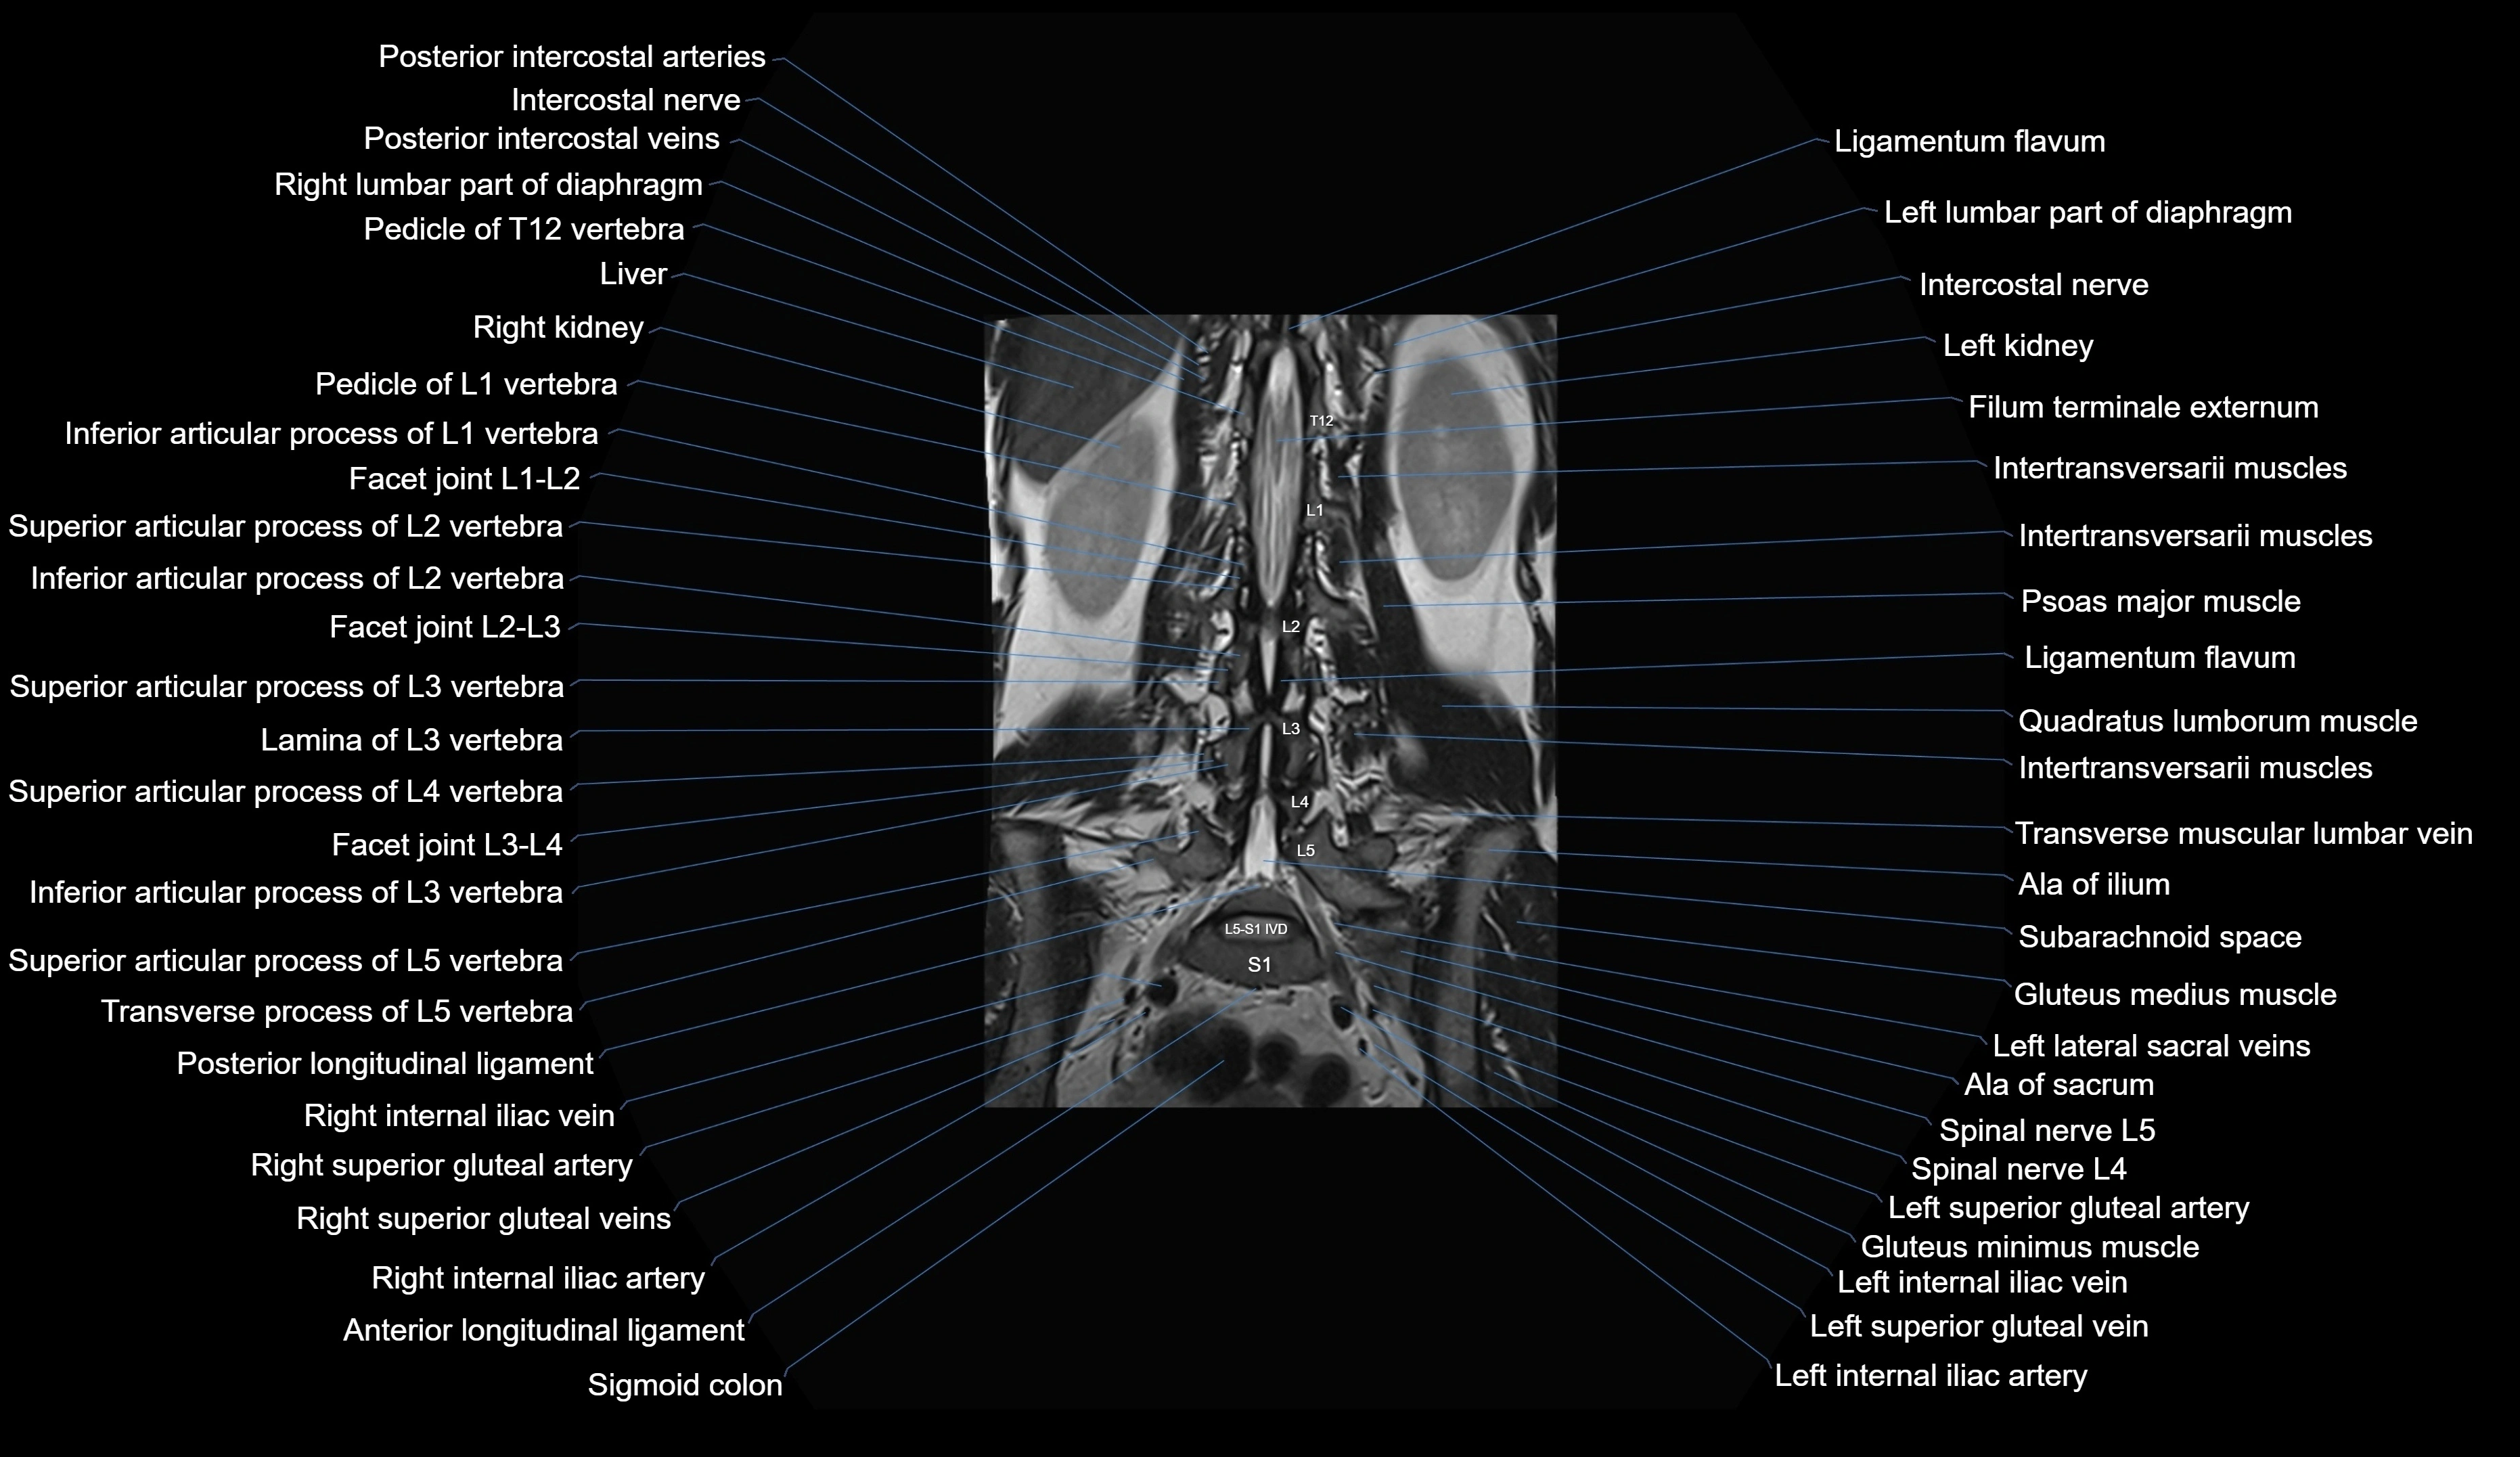

MRI images